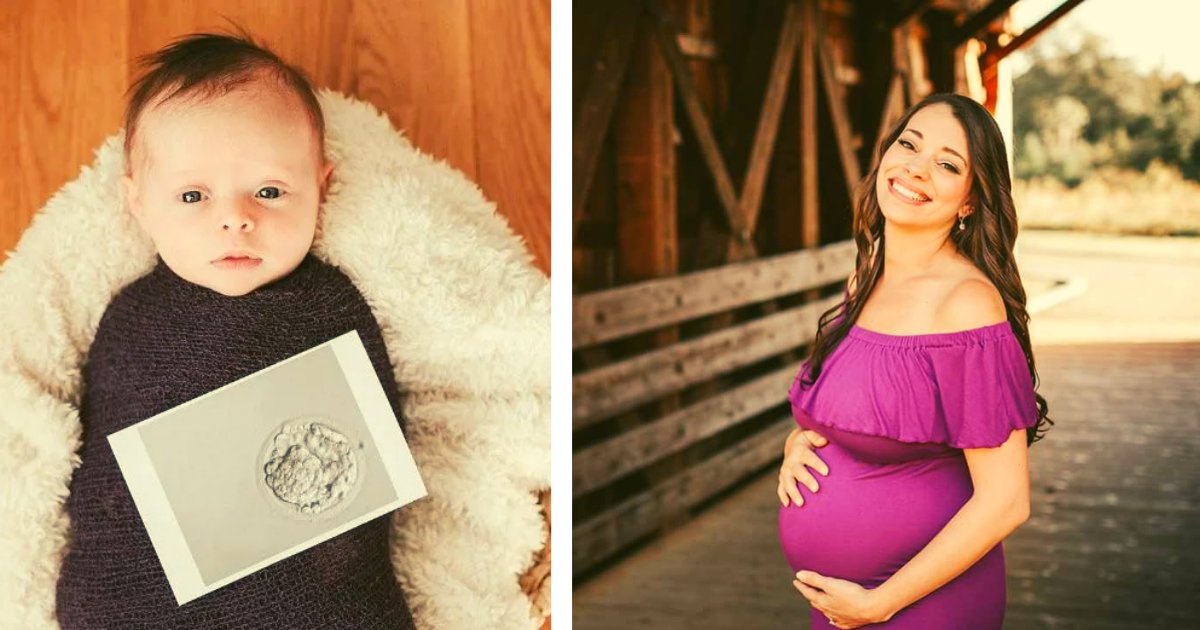

Así es el caso de la hija de Nancy y Chris Weiss, ambos de 43 años de edad, quienes pasaron más de dos años tratando de concebir antes de dar la bienvenida a su hija Luna hace tres meses.

Luego de cinco intentos fallidos de FIV y un embarazo químico, conocieron la adopción de embriones, donde se implanta un embrión congelado de una pareja exitosa.

A pesar de tener una tasa de éxito del 50%, Nancy se quedó embarazada al instante y después de investigar más sobre el procedimiento, se sorprendió al descubrir que la suya había estado congelada desde febrero del año 2004.

“Aún me sorprende cuando hablo de eso y tengo que explicarlo a otros. Intentar explicar la FIV es muy complicado, y mucho menos decirle a la gente que nuestra hija había estado congelada durante 16 años”, comentó Nancy.

“Nos tomó por sorpresa, no tenía idea de qué edad tenían los embriones cuando los adoptamos, pensé que habrían estado congelados durante un par de años, sin embargo, ella fue creada en febrero del 2004”, comentó.